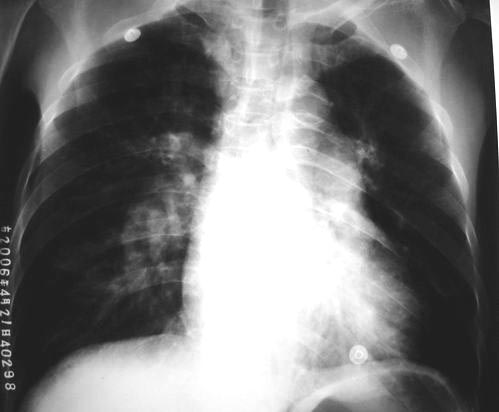

以下是引用lkc8963在2006-4-23 13:48:00的发言:[br]照片太黑无法观察肺野;仅见右下肺动脉干增粗,左肺门扩大;左下肺心后方似见片影(可以加照侧位或多轴位透视可以明确),右室轻大,上纵隔结构正常,说明有肺动脉高压,可能为肺心病所致,是否存在右心衰请结合临床,本片提示征象不足;[br]至于有无肺栓塞,本片无明确支持该病诊断,但不能除外因有肺动脉高压征象。pe多有基础病史,在影像学表现常为肺外周楔片影,右侧多见,和肺动脉增粗,如需排除,可做一个胸部ct增强了解管腔内有无充缺。